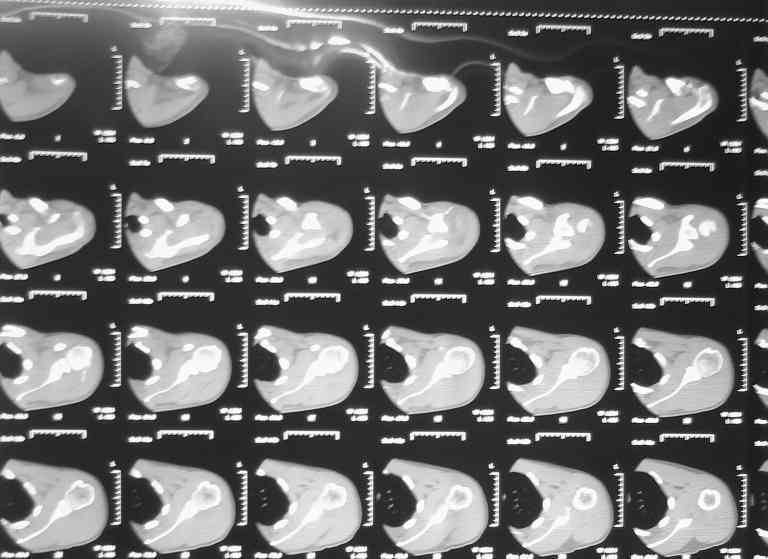

Падение на очередной гонке. По рассказу пациента произошел вывих плеча, который доблестные мед. работники города Саранска вправили "наживую" прямо на стадионе. Больного не фиксировали. По приезду зафиксировали плечо в наружной ротации (см. фото). Сделали Кт (На серии КТ с толщиной срезов 3 мм в левой плечевой кости определяется отрыв большого бугорка, определяется линейный перелом клювовидного отростка левой лопатки без смещения отломков (стрелки). В полости сустава- небольшое количество жидкости. В головке плечевой кости определяется эностоз. Определяется краевые костные разрастания акромиального конца ключицы.Заключение: перелом левой лопатки и плечевой кости.)Возникли вопросы по дальнейшей фиксации: Стоит ли давать отведение?Ну и дальнейшая тактика ведения больного.Спасибо за внимание.

Самое интересное (КТ) ну такого качества, ...

Нет ли там перелома глиноида? Опишите внутрисуставную жидкость макро- и микроскопически. Как долго после травмы? Обьективно что? пока одни вопросы, коллега.